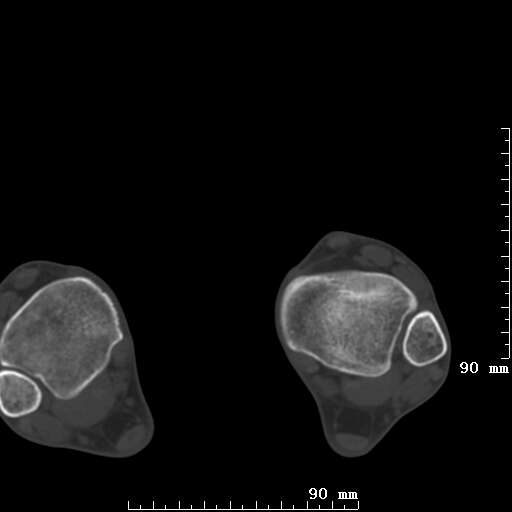

标题: CT19820:外伤一天,如何定性.男27Y [打印本页]

标题: CT19820:外伤一天,如何定性.男27Y

排除下创伤性关节炎吧,距骨有些囊变和硬化,周围韧带软组织有些机化、钙化。不是很像距骨无菌性坏死,感觉在关节面上的多,而不是距骨里面。

未见骨折及脱位像。距骨像是剥脱性软骨炎

支持!(踝关节距骨表面囊变和硬化 缺损)

距骨剥脱性软骨炎可能;踝关节创伤性关节炎?

未见明确新鲜骨折改变,距骨剥脱性软骨炎或踝关节创伤性关节炎可能。

距骨像是剥脱性软骨炎

关节周围多发高密度影,要结合病史

距骨像是剥脱性软骨炎。